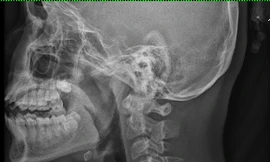

TPO - Bé gái 13 tuổi nhập viện trong tình trạng nuốt vướng, đau nhiều phần hạ họng sau khi ăn thịt gà. Nguyên nhân do bệnh nhi nuốt phải đoạn xương gà lớn, sắt nhọn khi vừa ăn vừa xem tivi.